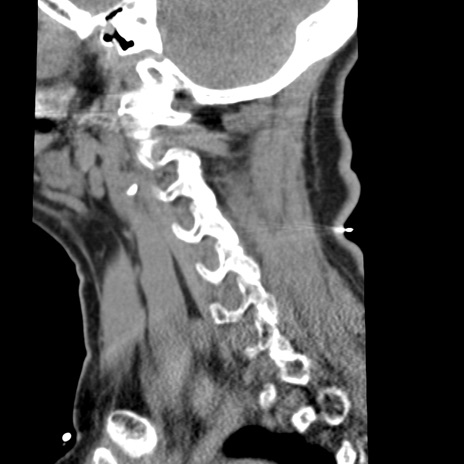

症例50 頚椎CT(矢状断像)

頚椎CT